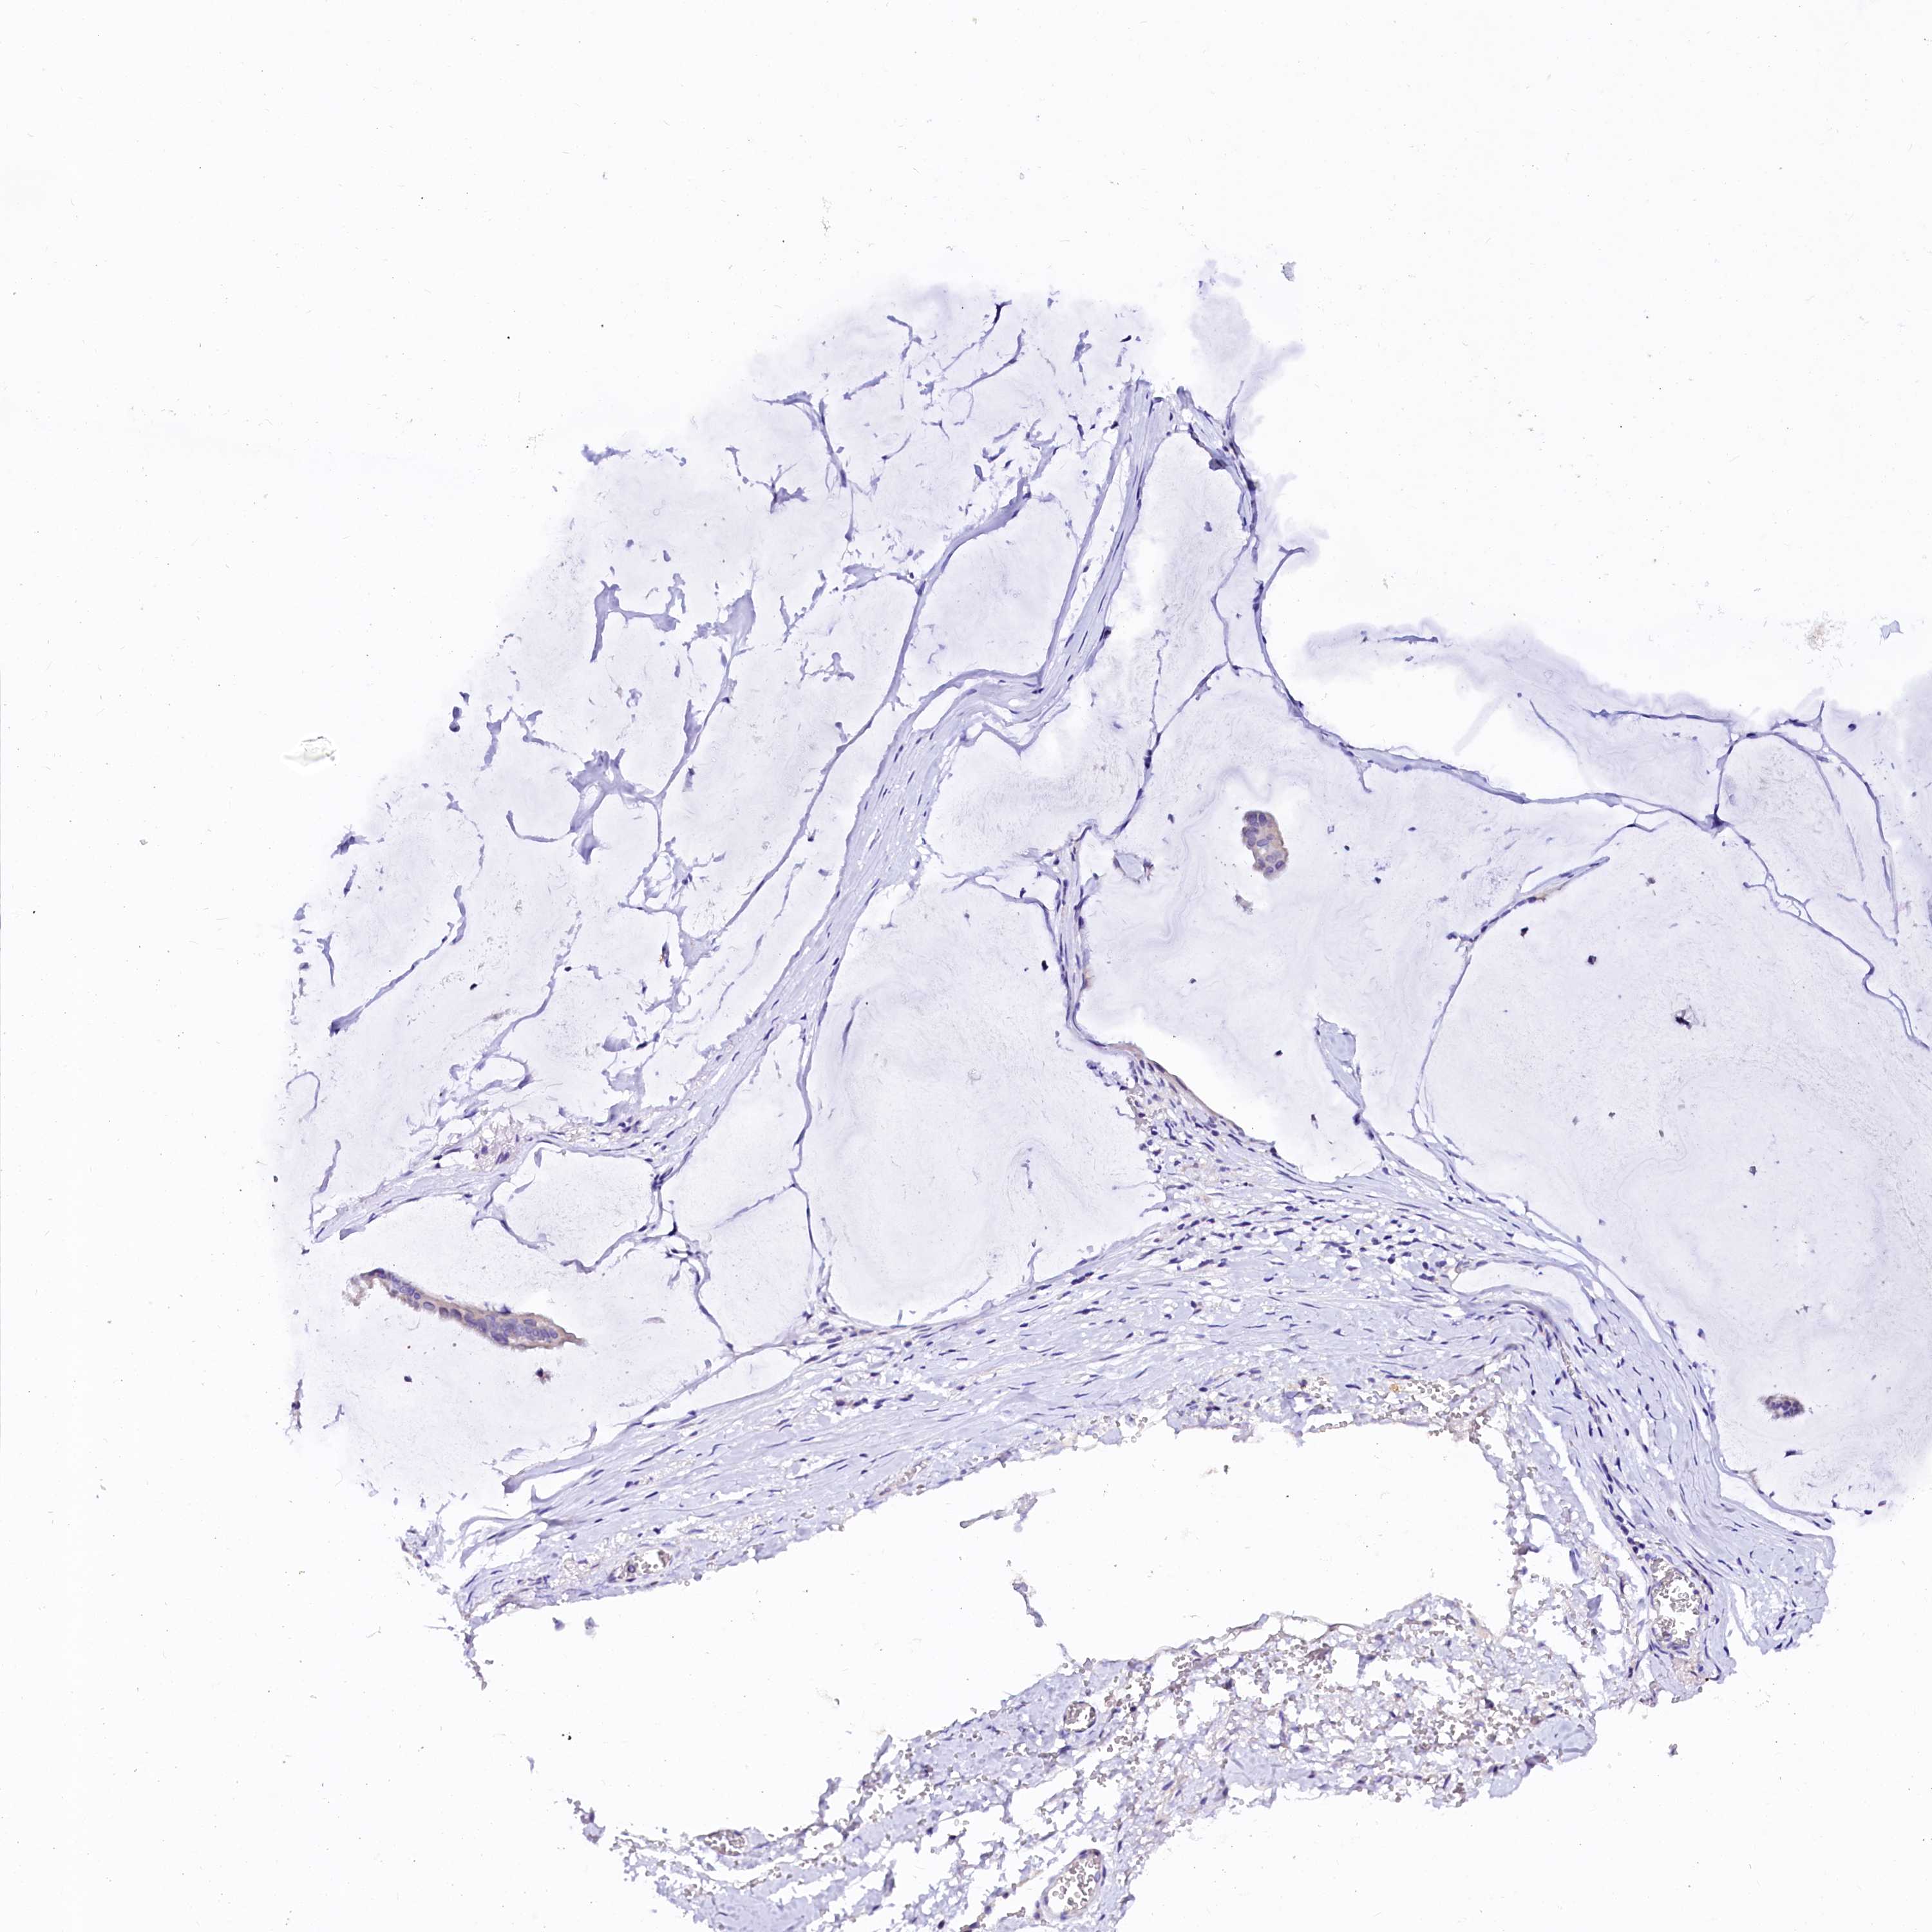

OVARIAN CANCER - Protein expressioni

A mouse-over function shows sample information and annotation data. Click on an image to view it in a full screen mode. Samples can be filtered based on level of antibody staining by selecting one or several of the following categories: high, medium, low and not detected. The assay and annotation is described here.

Note that samples used for immunohistochemistry by the Human Protein Atlas do not correspond to samples in the TCGA dataset.

Antibody stainingi

Antibody staining in the annotated cell types in the current human tissue is reported as not detected, low, medium, or high, based on conventional immunohistochemistry profiling in selected tissues. This score is based on the combination of the staining intensity and fraction of stained cells.

Each image is clickable and will lead to virtual microscopy that enables deeper exploration of all samples and also displays staining intensity scores, fraction scores and subcellular localization as well as patient and tissue information for each sample.

Antibody HPA039453

Cystadenocarcinoma, serous, NOS

Carcinoma, endometroid

Cystadenocarcinoma, mucinous, NOS

Carcinoma, NOS